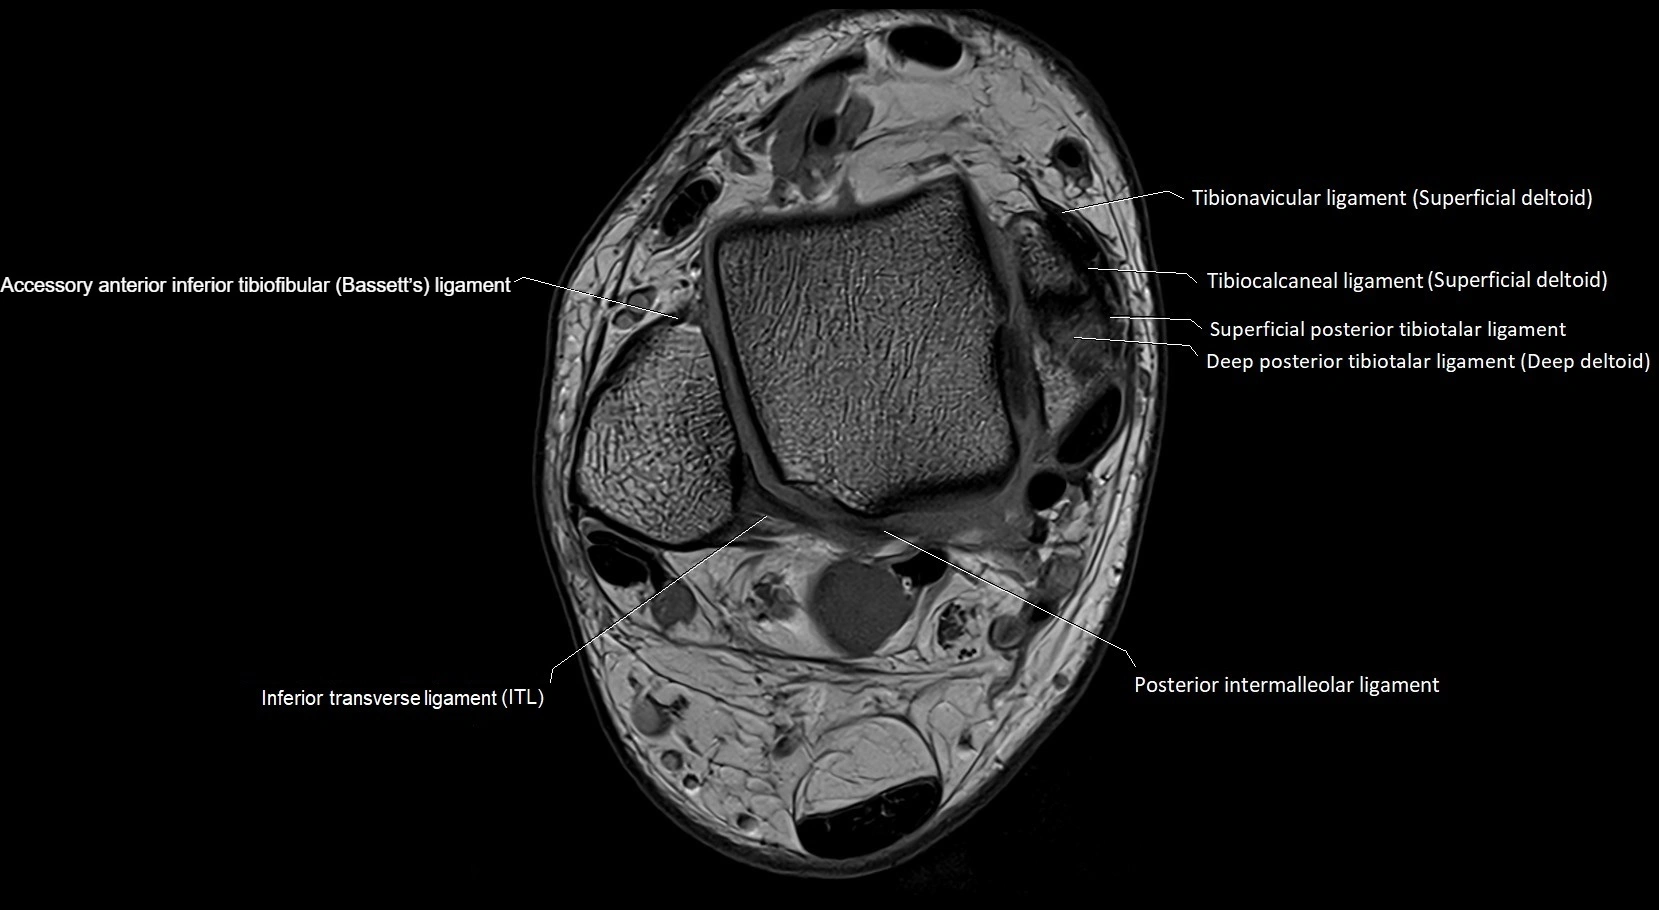

MRI image

image